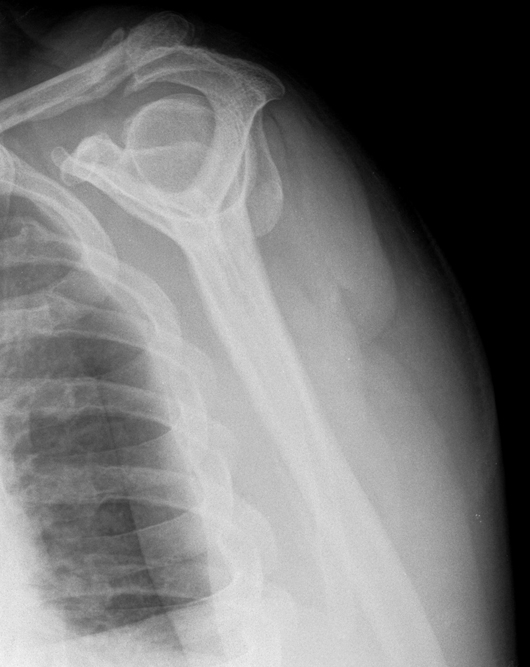

Sturz von der Treppe

So sieht es aus wenn man von der Treppe stürzt und auf eine 37 Jahre alte Verletzung fällt.

röntgenbild-Dezember-2017---2